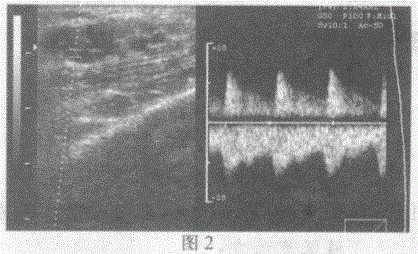

问题 临床资料:男,24岁,自述外伤后患肢肿胀、疼痛、麻木、乏力两年余。 超声综合描述:左肘部可见7.4cm×2.9cm形态不规则不均质回声区(图1),CDFI:内红蓝相间紊乱血流信号(彩图),可引出高速动脉频谱及静脉频谱(图2),动静脉之间相通。 {图2} 超声提示:

选项 A.左肘部脂肪瘤 B.左肘部假性动脉瘤 C.左肘部血管瘤 D.左肘部动静脉瘘(囊瘤型)

答案 D